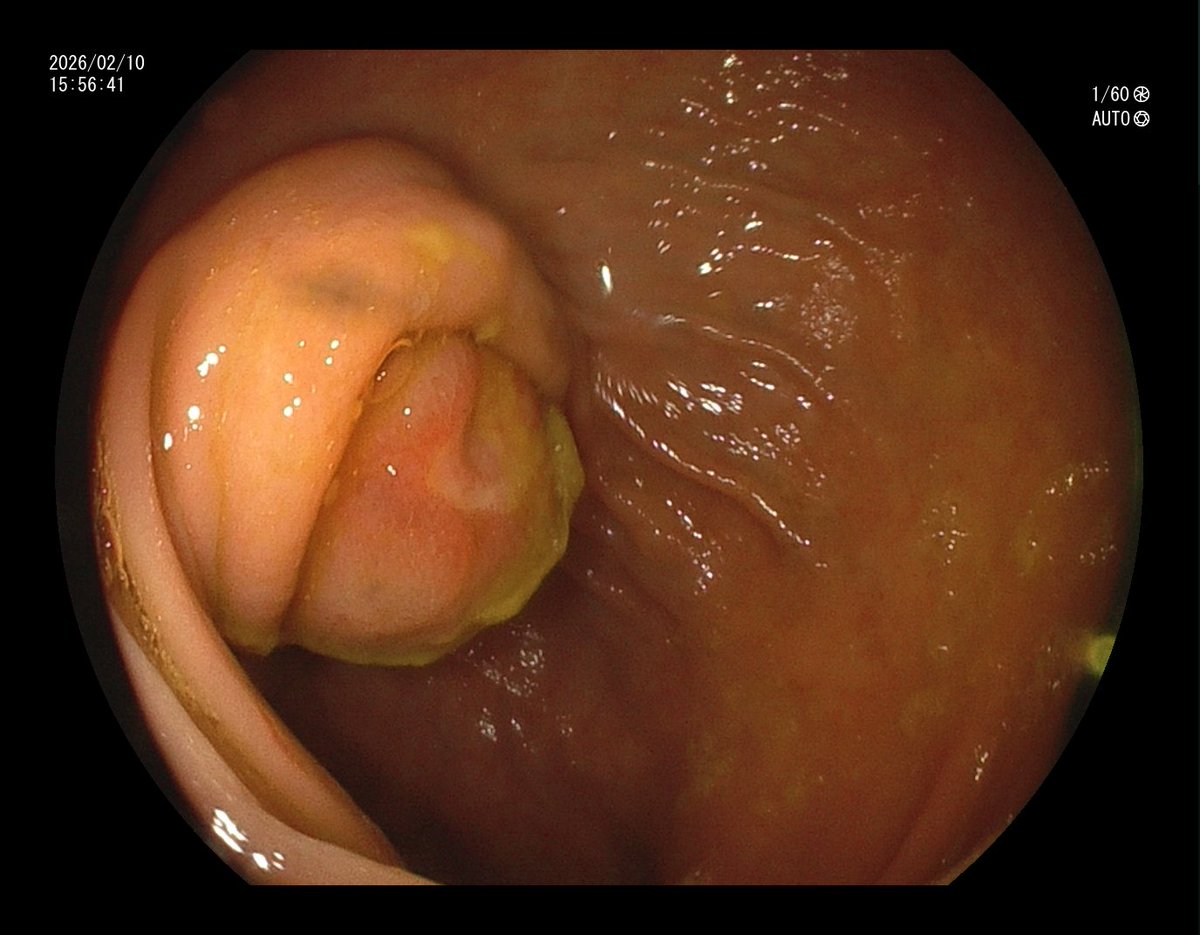

1. Antrum, low grade dysplasia. Removed via ESD. Specimen 43x32mm / dysplasia 20x13mm. R0